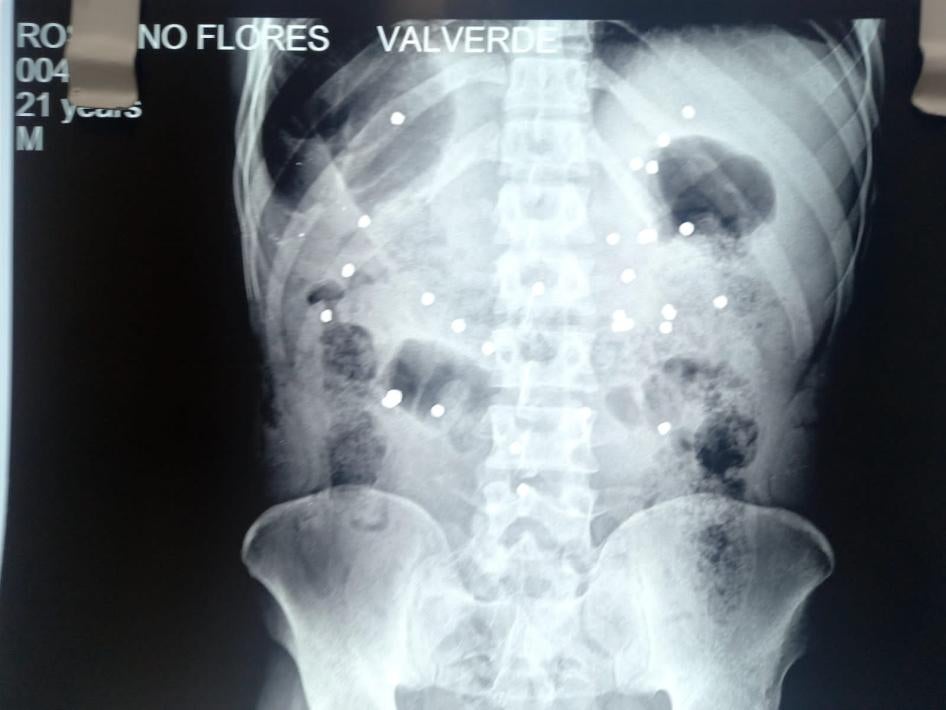

En enero de 2023, la policía disparó perdigones que causaron heridas que resultaron en la muerte de al menos cinco personas en Juliaca, Arequipa y Cusco. Las víctimas fueron impactadas por múltiples perdigones, lo cual indica que fueron disparados a corta distancia, ya que este tipo de proyectiles se dispersa con la distancia. En un caso, las imágenes de cámaras de seguridad verificadas por Human Rights Watch muestran a un agente de policía disparando a aproximadamente siete metros de distancia contra un joven que huía. Una radiografía mostró unos 30 perdigones en su cuerpo. Murió en marzo de 2023. Al menos 71 personas resultaron heridas por perdigones, según datos del Ministerio de Salud.